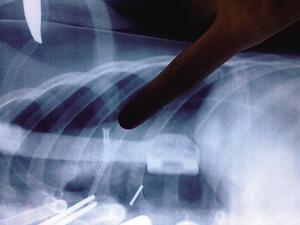

“CT结果显示,钉子已经射入心脏。血流入了心包腔。这样下去,孩子随时可能心跳骤停死亡。”儿童医院胸心外科主任吴春决定立即为浩浩实施手术抢救。吴春介绍,手术发现,钉子长约4厘米,从浩浩肋骨水平射入胸腔,在右心尖处进入心脏。所幸钉子顺利拔出,心包腔内血性积液也被清除。目前,浩浩在儿童医院胸心外科监护室,正在恢复中。